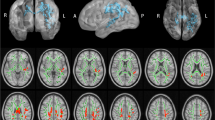

The dysregulation of brain iron homeostasis is closely relevant to a multitude of chronic neurological disorders. This study employed quantitative susceptibility mapping (QSM) to detect and compare whole-brain iron content between childhood epilepsy with centrotemporal spikes (CECTS) children and typically developing children.

Lower magnetic susceptibility was mainly observed in sensory- and motor-related brain regions in children with CECTS, including bilateral middle frontal gyrus, supplementary motor area, midcingulate cortex, paracentral lobule and precentral gyrus, the magnetic susceptibility of right paracentral lobule, right precuneus and left supplementary motor area were found to have positive correlation with the age at onset.

This study suggests that the potential iron deficiency in certain brain regions is associated with CECTS, which might be helpful for further illumination of potential pathogenesis mechanism of CECTS.